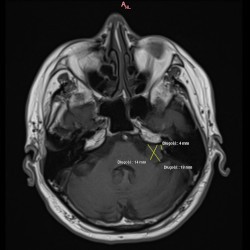

W dn. 15.09.2021 do Poradni Radioterapii zgłosił się chory z niedosłuchem lewostronnym i zaburzeniami równowagi. W wyniku MRI głowy w lewym kącie mostowo-móżdżkowym widoczna była lita masa silnie wzmacniającego się guza, który cienką wypustką wpuklał się do światła przewodu słuchowego wew.